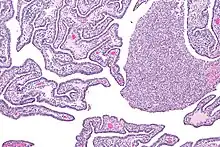

Micrograph of acute and chronic salpingitis. H&E stain.

Salpingitis can be acute, chronic, or subclinical.[4]